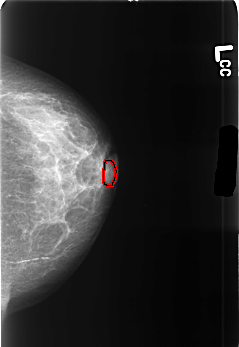

B_3445_1.LEFT_CC

FILE: B_3445_1.LEFT_CC.OVERLAY

TOTAL_ABNORMALITIES 1

ABNORMALITY 1

LESION_TYPE MASS SHAPE LYMPH_NODE MARGINS N/A

ASSESSMENT 2

SUBTLETY 3

PATHOLOGY BENIGN_WITHOUT_CALLBACK

TOTAL_OUTLINES 1

BOUNDARY